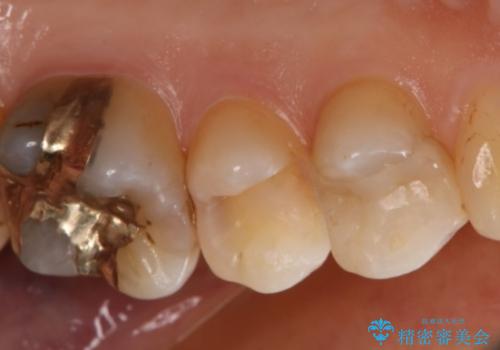

- 左上奥歯の銀歯のやり変えを希望された患者様です。

白くしたいとの事だったので形態・切削量を考慮し、セラミックインレーでの治療を計画しました。

保険材料と比較し、セラミックは劣化しない材料なので二次的な虫歯を防ぐことが出来ます。